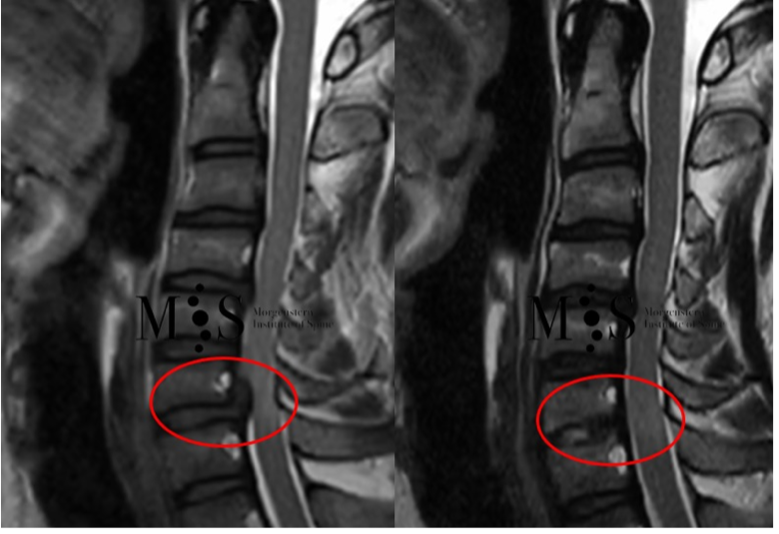

Realizada con éxito la primera cirugía endoscópica en España para solucionar la compresión medular cervical

Mediante un abordaje endoscópico, llevado a cabo por cirujanos del Morgenstern Institute of Spine del Centro Médico Teknon, es posible intervenir una columna cervical con una incisión en la piel de menos de 1 cm de longitud y una recuperación inmediata, y lograr el alta hospitalaria en menos de 24 horas.